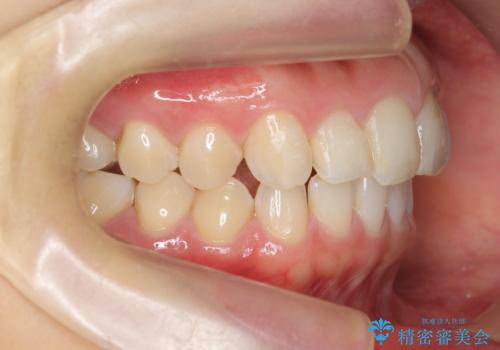

前歯のガタつきをきれいに マウスピース矯正治療

- 「前歯のガタつきをきれいにしたい。」と矯正治療を希望され来院されました。

前歯のガタつきをワイヤー部分矯正、上顎前突の咬合関係を後方移動することで理想的な咬合関係を確立します。

上顎の全体的な後方移動を実現するためにマイクロインプラントを併用したゴムかけを行ったことで理想的な咬合関係を確立することができました。